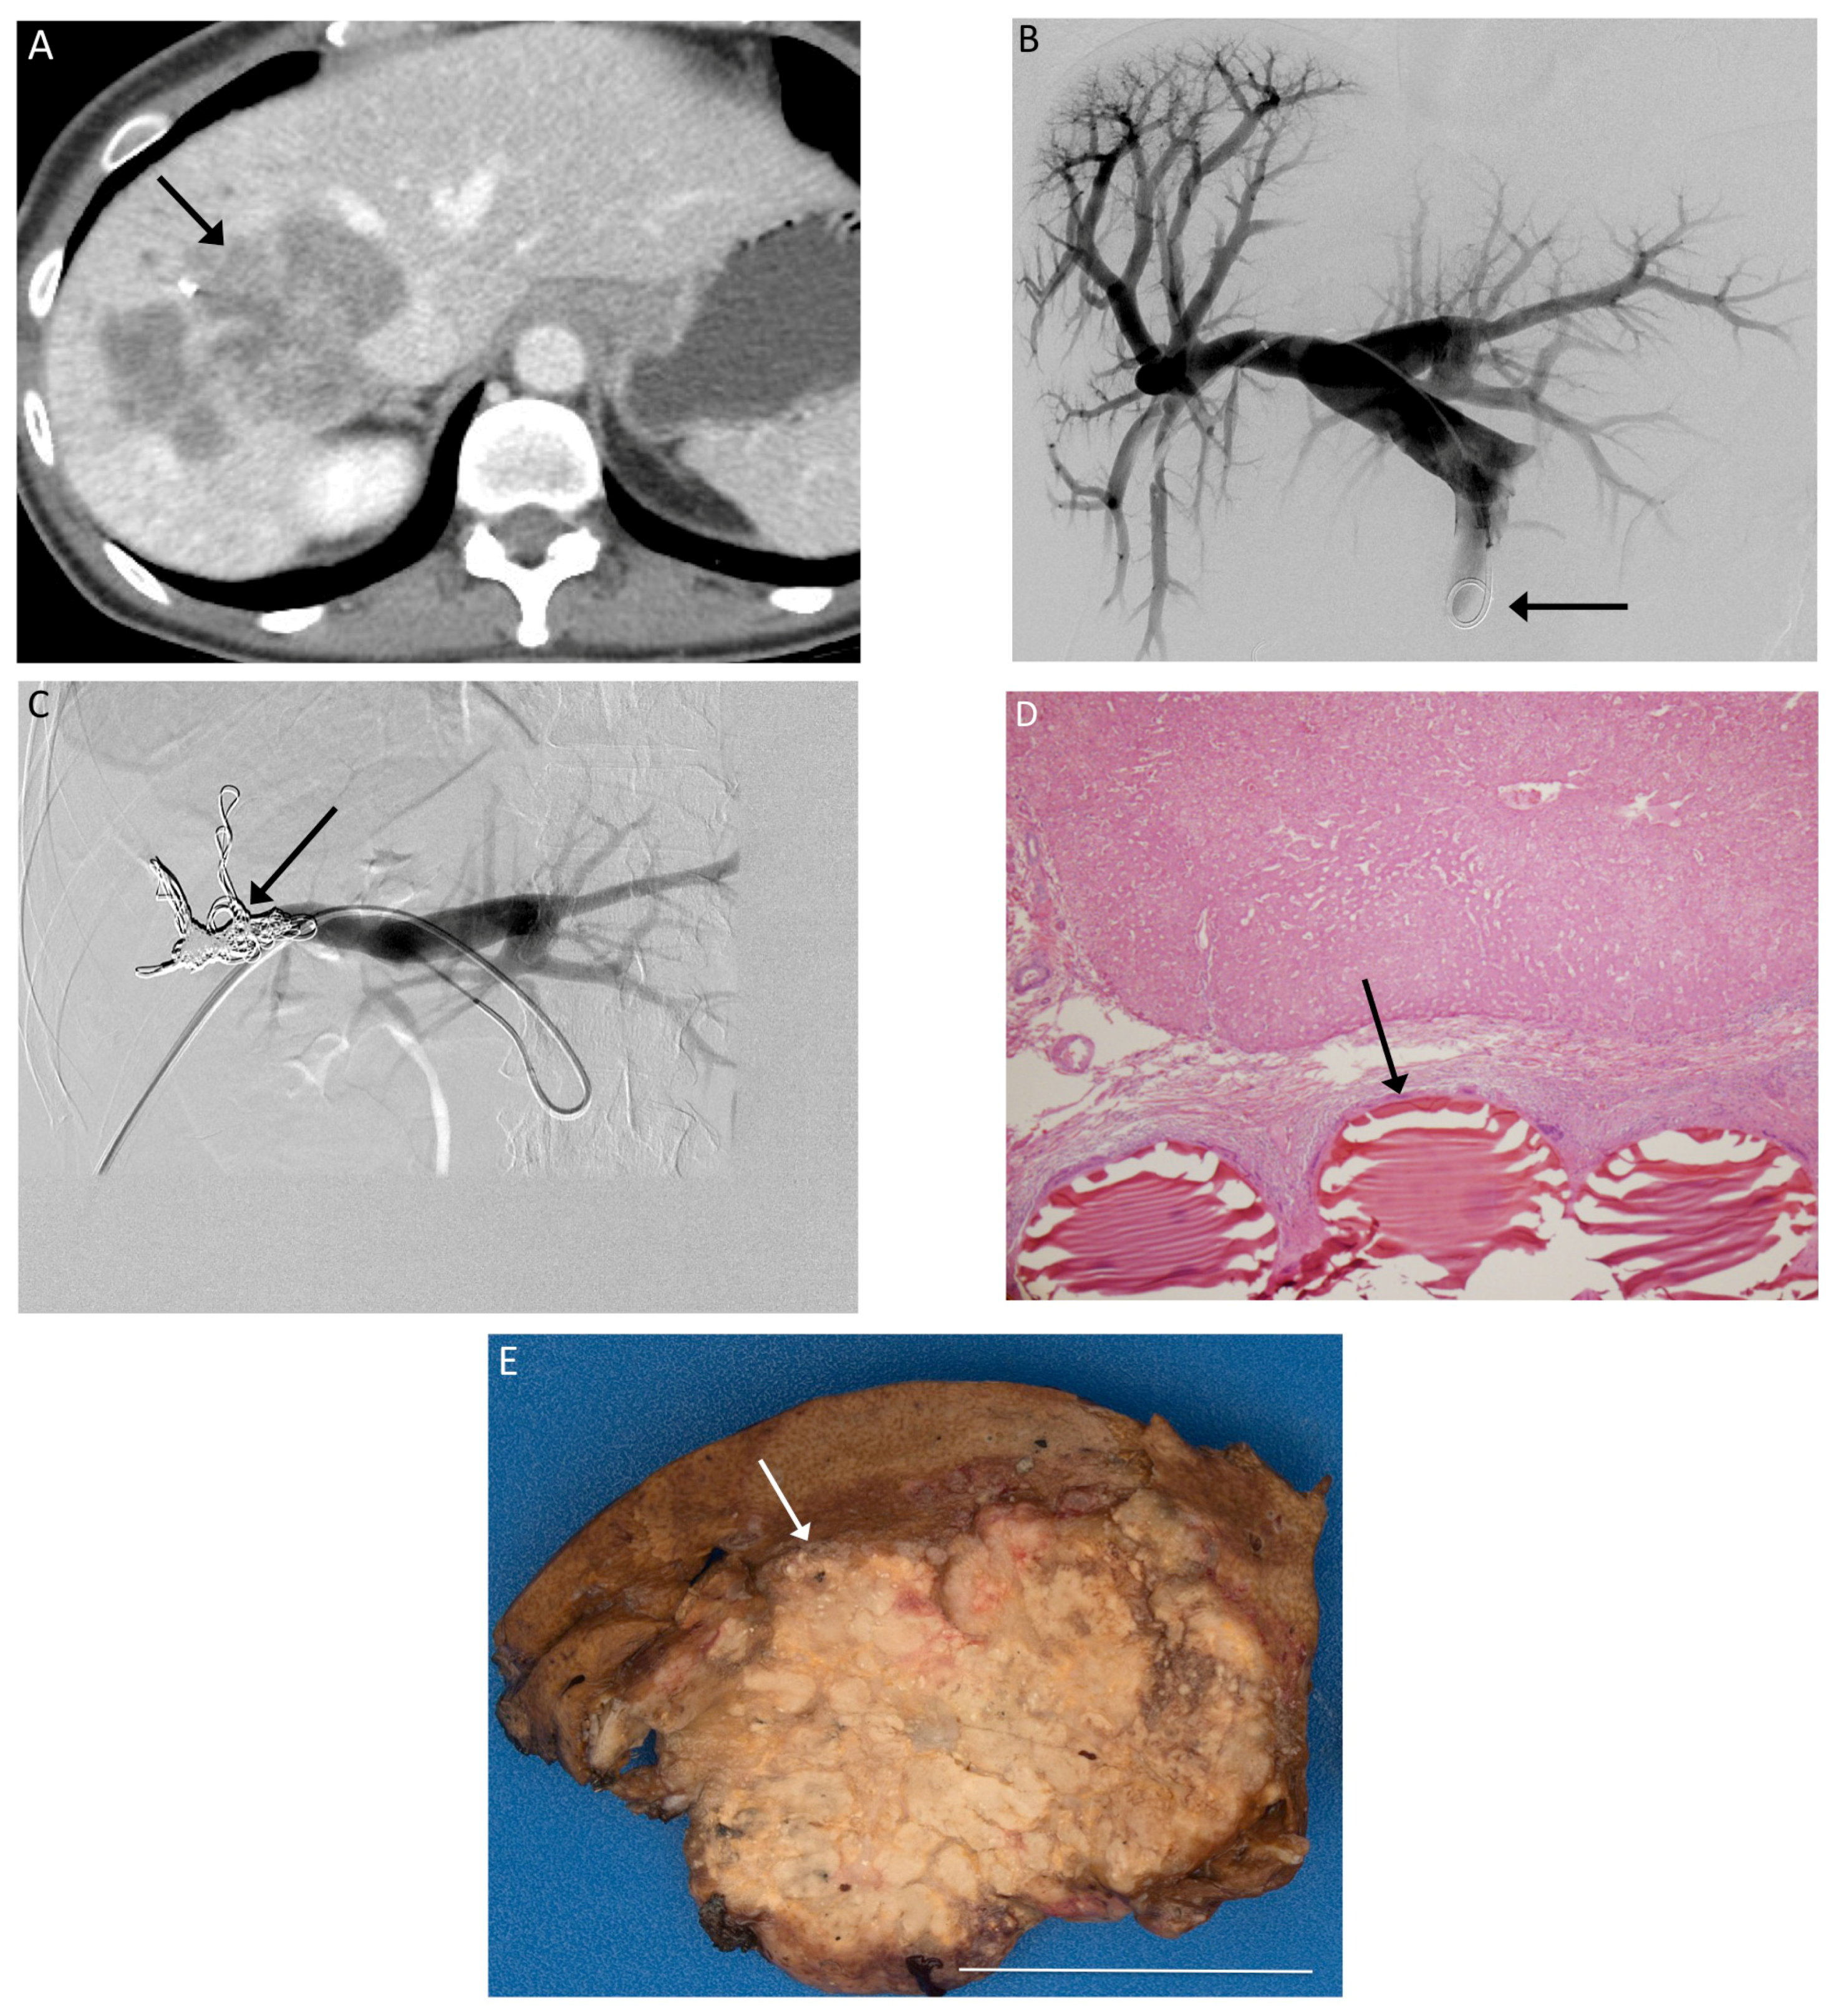

Pre-procedure magnetic resonance imaging (MRI) or computed tomograhy (CT) was performed 33 ± 5 days before PVE, whereas post-procedure MRI or CT was performed 33 ± 6 days after PVE. All PVEs involved the right portal vein prior to planned right hepatectomy. PVE was performed in standard fashion using a right lobe approach with both particles and metallic coils [14] (Figure 1). Images were assessed with TeraRecon (Foster City, CA, USA) by a radiologist blind to the patient’s treatments to calculate liver and tumor volumes before and after PVE.

Figure 1.

(A) Pre-procedure CT imaging demonstrates a right hepatic metastasis (arrow) from colorectal cancer, with a diminutive left lobe; (B) Tranhepatic portography (arrow) is obtained after portal access is achieved via the right portal vein; (C) The right portal branches have been embolized with particles and metallic coils (arrow); (D) 200× magnification H&E stain slide demonstrates Embosphere particles within a portal vein (arrow); (E) Gross specimen after right hepatectomy demonstrates particles within the embolized right hepatic lobe. White bar indicates 5 cm.